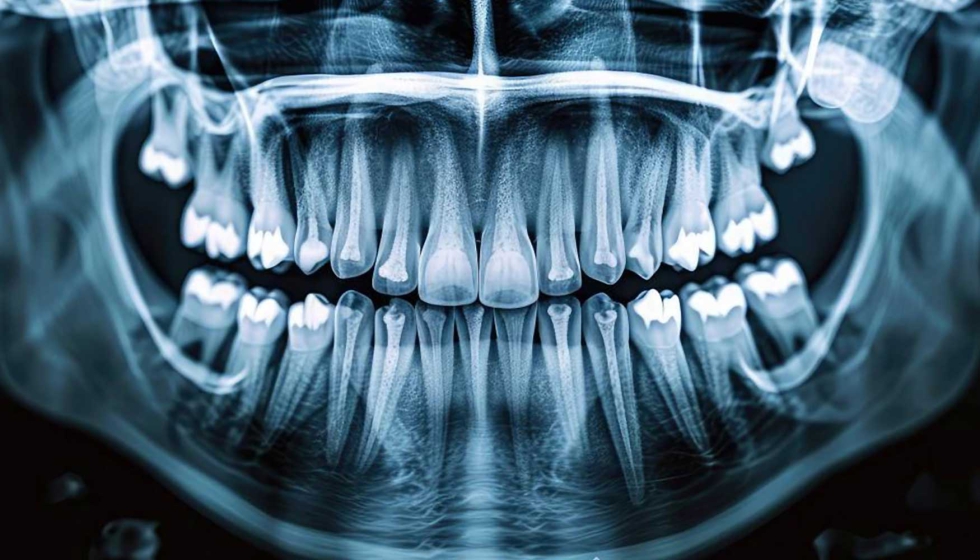

La nueva generación de implantes de titanio con moléculas bioactiva favorece su integración en el organismo. / Adobe Stock...

La nueva generación de implantes de titanio con moléculas bioactiva favorece su integración en el organismo. / Adobe Stock.